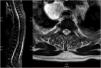

Initial laboratory findings are shown in (Table 1), which demonstrated pancytopenia, for which additional tests were ordered. The EMG revealed a four extremity, pure sensory axonal neuropathy, nevertheless, it only explained the sensitive symptoms, not the motor ones. The MRI (Fig. 1) showed an extensive longitudinal myelitis, from C2 until the conus medullaris, with bilateral and symmetric, posterior and lateral cord involvement, with no contrast enhancement; derived from this finding, additional serum tests were ordered (Table 1), ruling out an infectious, autoimmune or paraneoplastic etiology. It was noted that vitamin B12 levels were within normal limits (200–300 pg/mL), however, it was thought of the possibility that both the pancytopenia and the myelopathy could be explained by the same origin, and homocysteine and methylmalonic acid (MMA) levels were ordered, whose values were 26 μmol/L (normal: 5.56–16.2 μmol/L), and 350 nmol/L (normal: 73–270 nmol/L), respectively; meaning a clear vitamin B12 deficiency. Additionally, anti-intrinsic factor antibodies were ordered, which came back elevated (16.2 U/ml; normal: <6 U/ml); and an upper gastrointestinal endoscopy, which showed atrophic gastritis in the body and fundus. All of the above makes up the diagnstic of subacute combined degeneration, pure sensory axonal neuropathy and pancytopenia secondary to vitamin B12 deficit caused by pernicious anemia. It was initially treated with intramuscular cyanocobalamin together with folic acid.